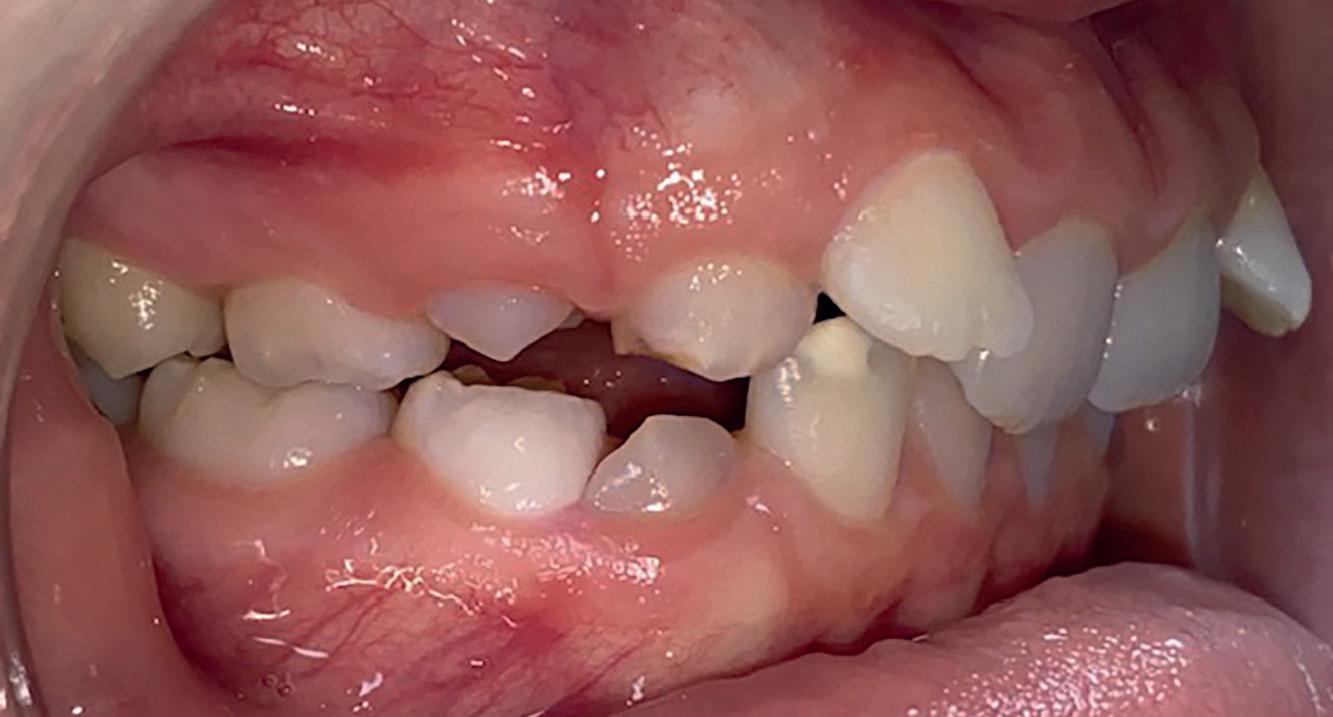

Casus in Proces

Patiënt Sonnie presenteerde zich met ernstig ruimtegebrek ter hoogte van de 13 en 44 en een kruisbeet aan de zijde van de 15 en 14. De 13 was ectostematisch gepositioneerd, waardoor extractie aanvankelijk als mogelijke behandeloptie werd overwogen.

Door een combinatie van verbreding en het inzetten van een D-gainer wordt de benodigde ruimte gecreeerd om alle elementen correct in de tandboog te positioneren, waardoor extracties kunnen worden vermeden. De behandeling zal binnen twee jaar worden afgerond; het eindresultaat wordt gedeeld in editie 2 van ons magazine.

Start behandeling

Midden behandeling

Laatste fase